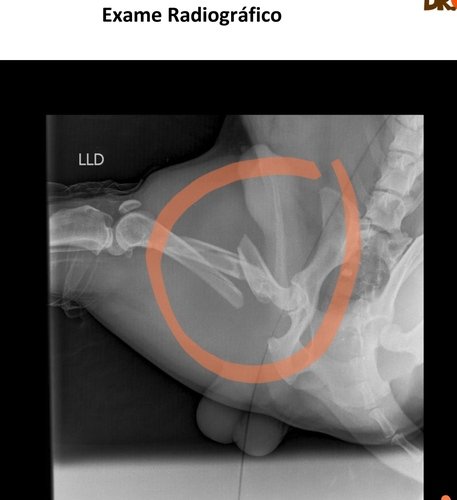

Fui atropelado no dia 17/07. Passei por duas cirurgias. Tive várias fraturas no fêmur e na região pélvica, estou anêmico e com alteração no fígado.